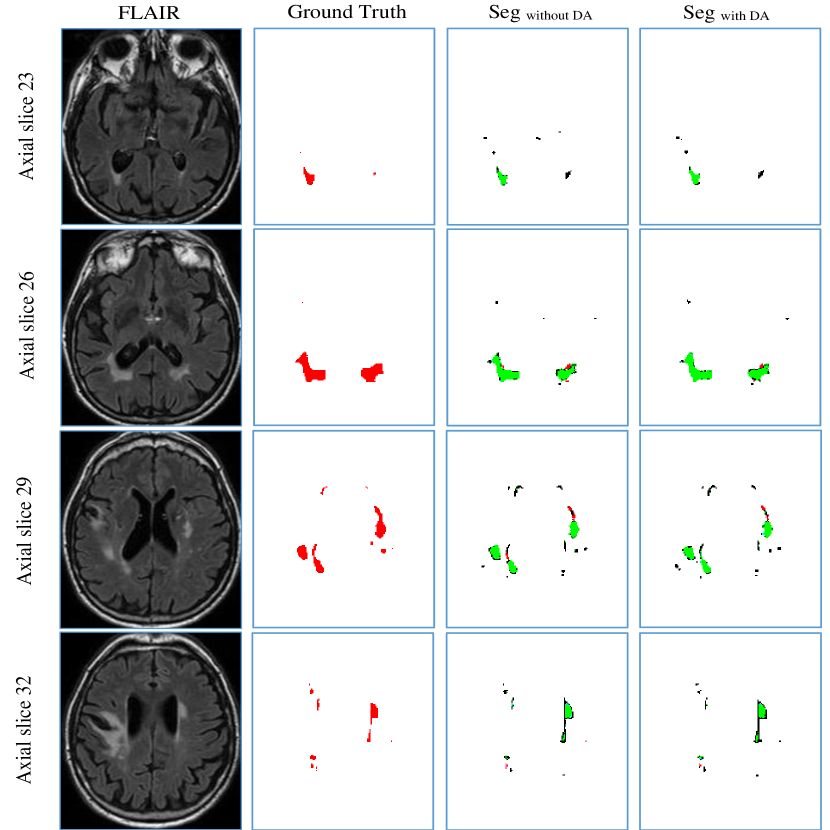

The intention of data augmentation is generating training samples with different distributions to teach network learning desired invariance and robustness. We evaluated this technique using the cross-scanner evaluation as discussed in Section 5.3. The same experimental setting was used.

Table S5 to Table S7 in supplemental material report extensive results. They show that using data augmentation slightly improved segmentation results on most of the metrics. Figure 11 shows the segmentation results of a case from Utrecht tested by the model trained on Singapore and GE3T. We observed that some false positives with small volumes were removed by employing data augmentation after comparing the column SegwithoutDA to SegwithDA, suggesting the model achieved robustness to small lesions. We further performed Wilcoxon signed rank test on the 60 cases. The improvements on H95, Recall and F1-score are statistically significant, giving p-values smaller than 1 ×104absentsuperscript104\times 10^{-4}.

Refer to caption

Figure 11: Sample segmentation result on Utrecht 04. From top to bottom: four axial slices of the same subject. From left to right: FLAIR MR images, the associated ground truth, segmentation result without using data augmentation and segmentation result with data augmentation. In column SegwithoutDA and SegwithDA, the green area is the overlap between the segmentation result and the ground truth, the red ones are the false negatives, and the black ones are the false positives. (Best viewed in colour)